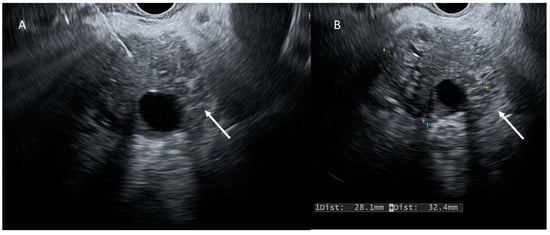

- Kitano, M.; Yoshida, T.; Itonaga, M.; Tamura, T.; Hatamaru, K.; Yamashita, Y. Impact of endoscopic ultrasonography on diagnosis of pancreatic cancer. J. Gastroenterol. 2018, 54, 19–32. [Google Scholar] [CrossRef] [PubMed]

- Zhang, L.; Sanagapalli, S.; Stoita, A. Challenges in diagnosis of pancreatic cancer. World J. Gastroenterol. 2018, 24, 2047–2060. [Google Scholar] [CrossRef] [PubMed]

- Capurso, G.; Signoretti, M.; Valente, R.; Arnelo, U.; Lohr, M.; Poley, J.-W.; Fave, G.D.; Del Chiaro, M. Methods and outcomes of screening for pancreatic adenocarcinoma in high-risk individuals. World J. Gastrointest. Endosc. 2015, 7, 833–842. [Google Scholar] [CrossRef]

- Jang, D.K.; Song, B.J.; Ryu, J.K.; Chung, K.H.; Lee, B.S.; Park, J.K.; Lee, S.H.; Kim, Y.T.; Lee, J.Y. Preoperative diagnosis of pancreatic cystic lesions: The accuracy of endoscopic ultrasound and cross-sectional imaging. Pancreas 2015, 44, 1329–1333. [Google Scholar] [CrossRef]